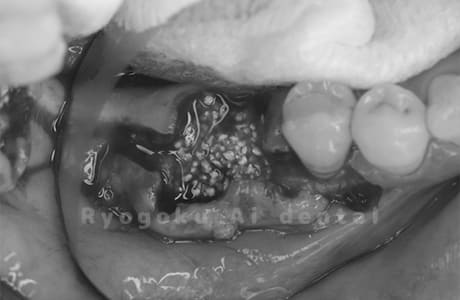

Case12

- 原因

- 左下7番歯牙破折

-

- 治療内容

- インプラント治療

- 治療費用

- 約600,000円

左下の奥歯が痛いとのことでご来院された患者様です。歯が完全に割れており、保存が不可能であったため、抜歯を行い、その際に骨に変わるお薬を入れ、十分な治癒を待ってからインプラント治療を行いました。経過良好で、大変満足されました。

<リスク・副作用>

治療後、痛みや違和感、出血、腫れなどが出る事があります。喫煙者、糖尿病などの方の場合、歯が生着しない場合があります。